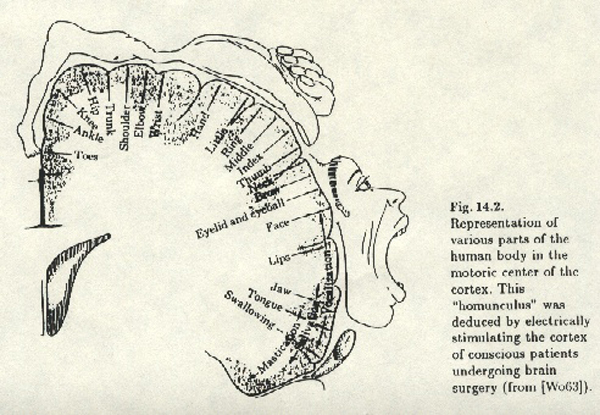

My interests span the information, physical and cognitive sciences, and their nexus, e.g. complexity.